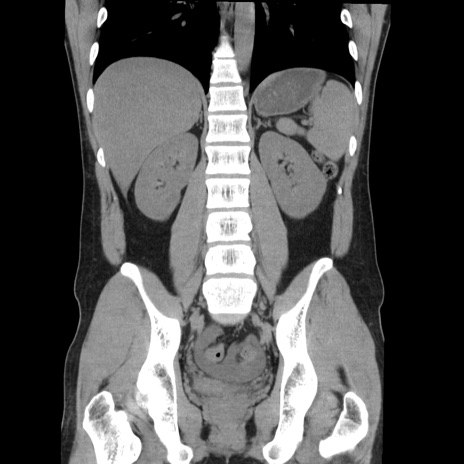

症例36(冠状断像)

【症例】20歳代 男性

【主訴】心窩部痛

【現病歴】今朝より上腹部痛あり。一旦軽快していたが再度出現したため救急要請。昨日夕に白身の魚を含む刺身を食べた。

【身体所見】BP 136/89mmHg、HR 74/min、BT 37.0℃、腹部:膨満、軟、心窩部に圧痛あり。反跳痛なし、筋性防御なし、腸雑音やや亢進あり。

【データ】WBC 17700、CRP 0.48